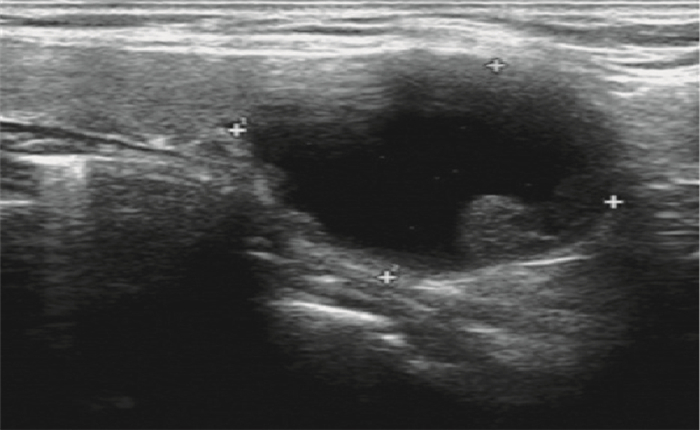

6例患者術前均行超聲檢查(表 1),其中4例提示甲狀腺左葉囊腫(圖 1);1例提示甲狀腺左葉下極下方低回聲團(圖 2);1例提示甲狀腺右葉結節伴微小鈣化灶,甲狀腺左葉下極下方囊性包塊。2例行甲狀腺ECT檢查,1例顯示甲狀腺左葉下極“冷”結節,1例顯示甲狀腺雙葉核素分布不均勻。術前診斷見表 1。

示甲狀腺左葉下極囊性腫物(30 mm×29 mm),邊界清楚,內呈液性??圖 2 ??示甲狀腺左葉下極下方低回聲團(10 mm×6 mm),邊界清楚,形態欠規整

Ultrasonography image showed a cyst (30 mm×29 mm) in the left lower thyroid lobe, with clear boder ??Figure 2?? Ultrasonog-raphy image showed a low echo mass (10 mm×6 mm) inferior to the left lower thyroid lobe, with clear boder and irregular shape